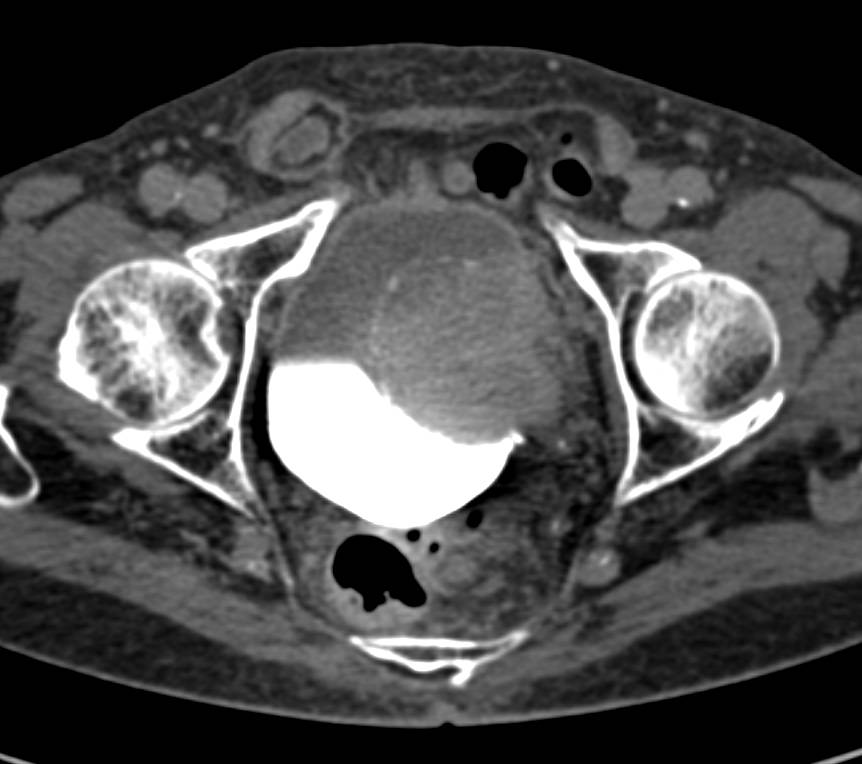

Primjer ispitivanja hematurije CT urografijom kroz slučajeve!

Slučaj 1. Karcinom urotelnih ćelija.

Slučaj 2. Karcinom mokraćne bešike.

Slučaj 3. Kamenci u bubrezima